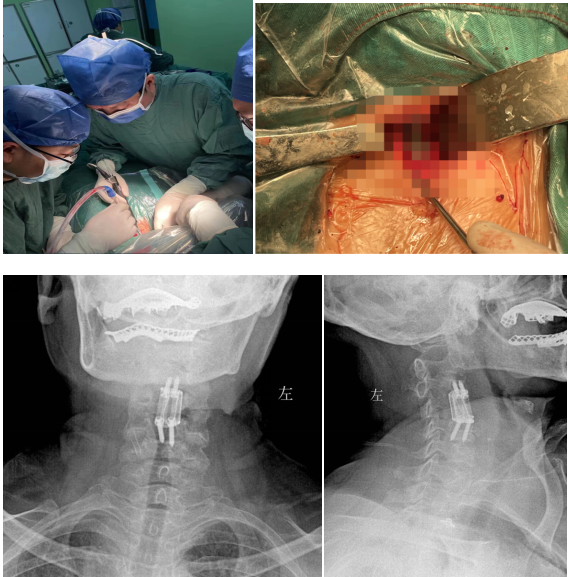

經(jīng)過多學(xué)科會診(MDT),完善術(shù)前相關(guān)準(zhǔn)備后,由蘇光輝主任主刀,帶領(lǐng)團隊錢軍、鄧三東等,精準(zhǔn)完成病灶清除、椎管減壓、植入3D打印cage等流程,在麻醉師、手術(shù)室的全力配合下,整臺手術(shù)一氣呵成,手術(shù)順利。

經(jīng)過周密細致的術(shù)前討論,脊柱外科團隊最終決定為該患者擬行頸椎病灶清除、椎管減壓+植骨融合術(shù),考慮患者高齡,又有骨質(zhì)疏松,為更好保障重建穩(wěn)定性,采用3D打印進行術(shù)前規(guī)劃設(shè)計假體進行植入,此款融合器是國內(nèi)首款SLM激光打印融合器,具有解剖匹配、骨融合確切等優(yōu)勢,為取得優(yōu)良手術(shù)效果打下了堅實基礎(chǔ)。